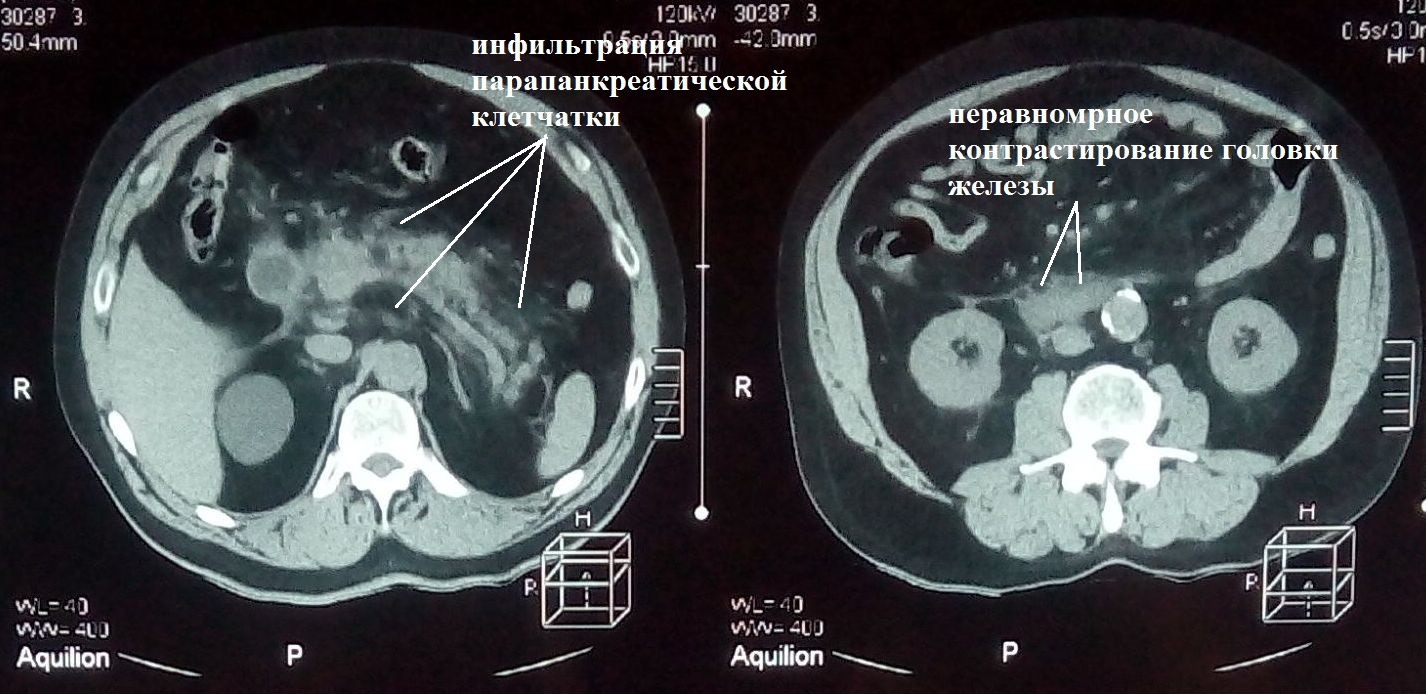

Пациент М., 69 лет, поступил в клинику 21.09.2017 г. на первые сутки от начала заболевания. При клинико-инструментальном обследовании установлен предварительный диагноз: острый тяжелый панкреатит, оментобурсит (рис. 1).

Рис. 1. КТ брюшной полости больного М. от 21.09.2017 г. (1-е сут болезни)